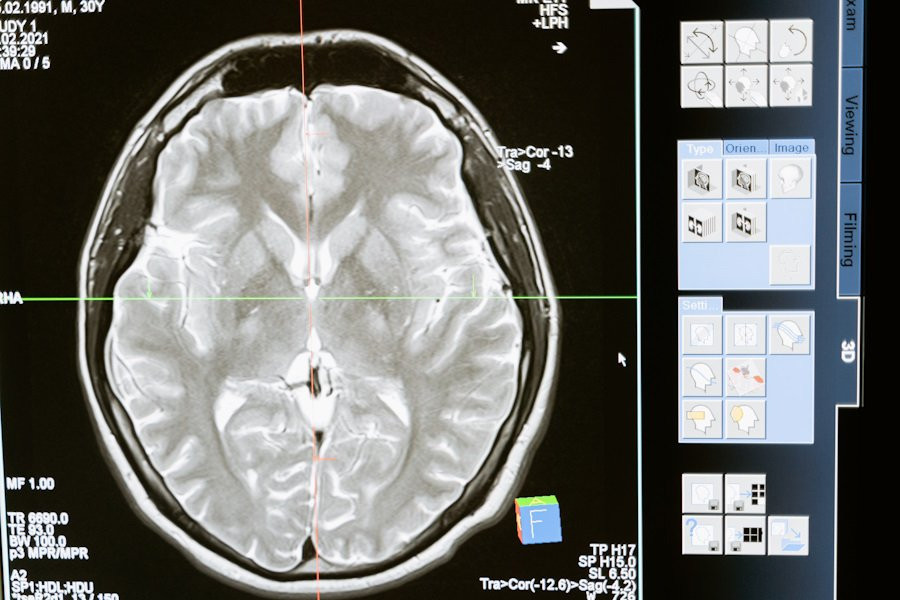

Эпилепсия — это заболевание, при котором мозг работает неправильно, вызывая приступы, потому что гены не работают должным образом. Одним из таких генов является CDKL5, который кодирует фермент (особый белок), необходимый для правильной работы мозга.